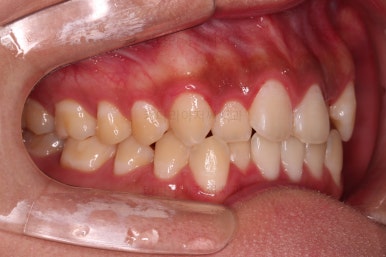

부산치아교정치과 초진 시 입안의 모습입니다.

앞니쪽이 위아래 모두 삐뚠 상태였고요.

왼쪽은 덧니로 툭 튀어나가 있고, 상대적으로 작은 앞니는 안으로 말려 들어가 아랫니와도 거꾸로 물리는 상태였습니다.

어금니도 물론 약간 삐뚤긴 하지만 앞니만큼 심한 상태는 아니었고 맞물리는 기능도 큰 불편함은 없으신 상태였습니다.